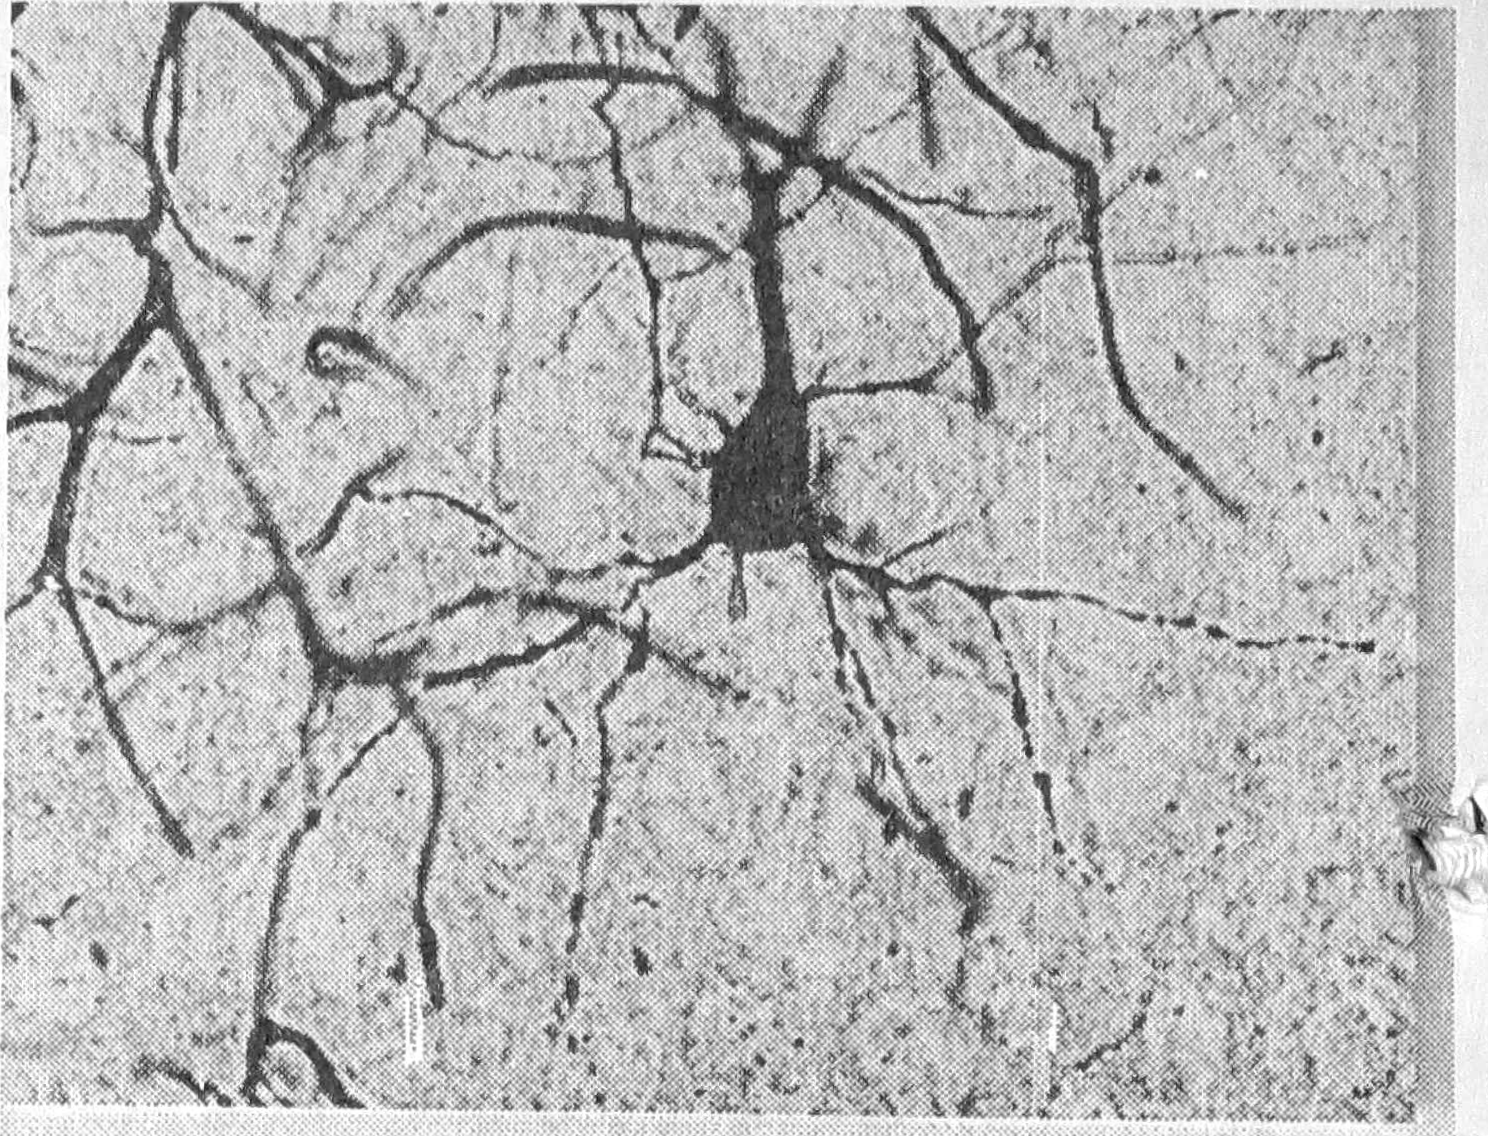

Рис. 1. Ультраструктура нейрона слоя V сенсомоторной коры через один час после одного аудиогенного припадка, х 12000.

При исследовании коры мозга крыс через час после одного аудиогенного припадка определялось набухание многих корковых нейронов в сочетании с периферическим хроматолизом. Ядра большинства клеток были светлыми, умеренно набухшими, изредка смещенными к периферии клеточного тела. В части гипохромных клеток отмечались признаки репарации в виде смещения ядрышка к периферии ядра, наличия в цитоплазме околоядерного гиперхромного пояса. Встречались отдельные клетки с явлением цитолиза и кариоцитолиза и группы гиперхромных нейронов. На ультраструктурном уровне наблюдались обеднение цитоплазмы органеллами, расширение цистерн эндоплазматической сети, подчас неравномерное, отек отдельных или большинства цистерн аппарата Гольджи, умеренное набухание отдельных митохондрий, увеличение числа лизосом и ядерных пор (рис. 4). Такие изменения популяций нейронов хвостатого ядра обнаруживались при двигательном возбуждении, вызванное фенамином [5]. Дендриты и шипиты корковых нейронов в основном были хорошо импрегнированы, лишь иногда их импрегнация снижалась. В дендритах отмечалось уменьшение числа микротрубочек и нейрофиламентов вплоть до их полного отсутствия и появления вакуолей в дендроплазме. Темные нейроны выявлялись редко, что может указывать на нарушение первичной интеграции приходящих к нейрону импульсов. Имели место умеренное набухание астроцитов с тонкими отростками и явлениями гиперкариохромии. Плотные олигодендроциты не имели видимых отростков. Среди микроглиоцитов встречались формы с фрагментированными отростками. Наблюдалась дистония и расширение просвета части корковых сосудов, набухание сосудистых стенок, периваскулярные отеки, единичные диапедезные кровоизлияния.